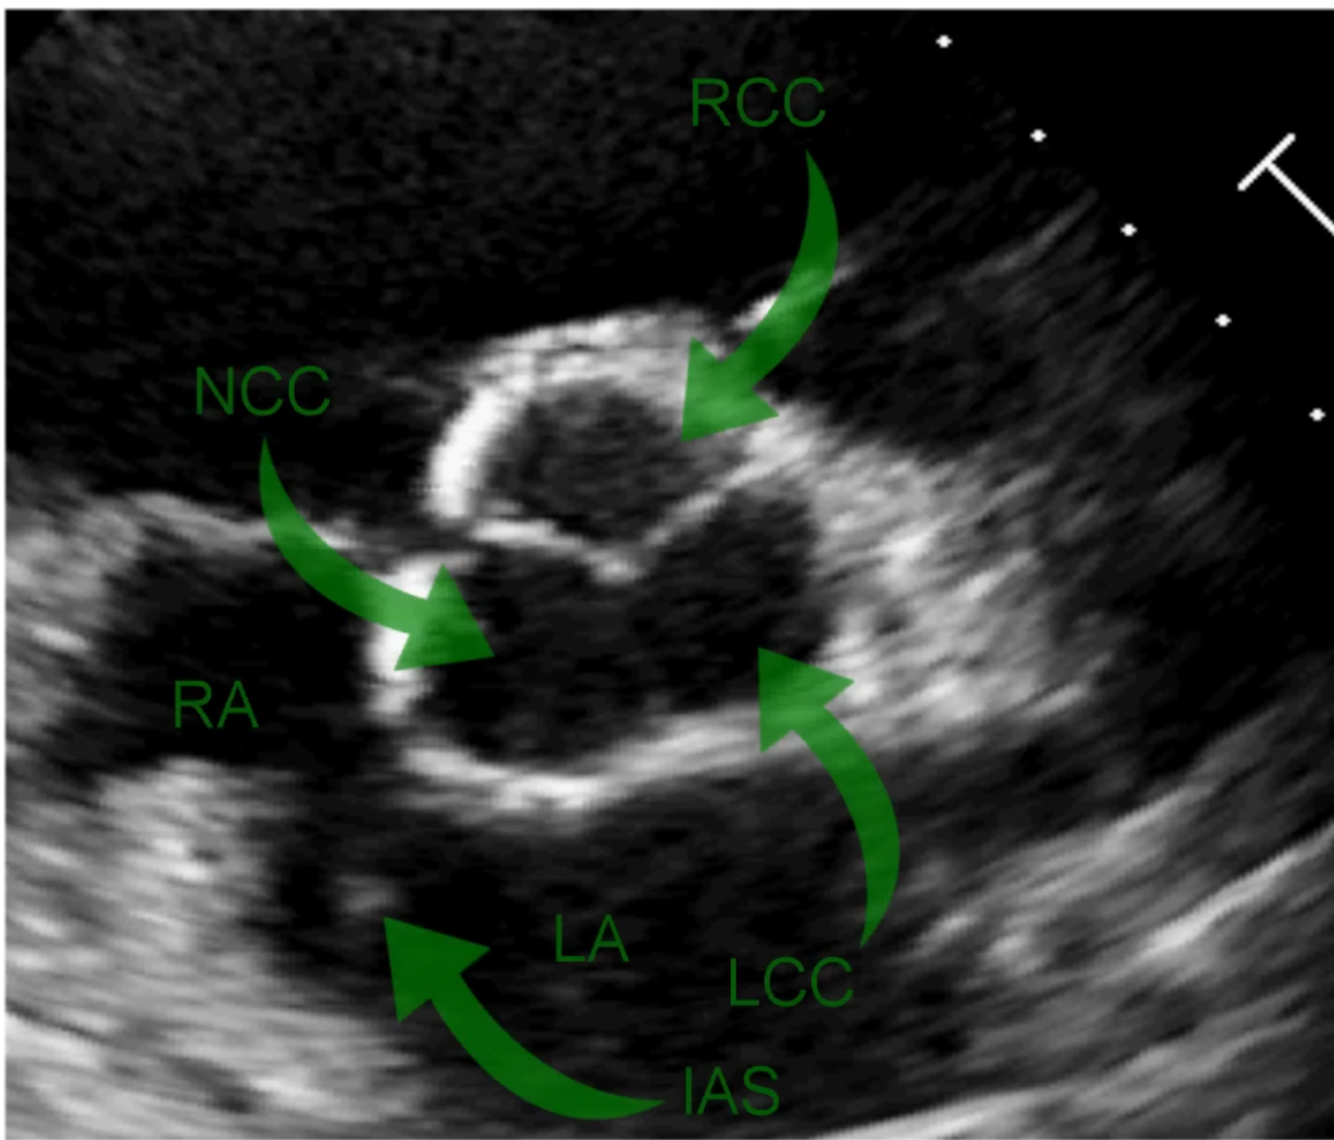

What are the name of the aortic valve cusps?